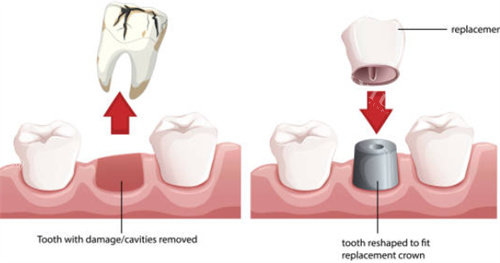

关键词:个性化方案+“留牙派”

张元伟院长是“能留就不拔”的拥趸,先拍CBCT给你讲“保牙”概率,实在保不住才动刀,因此收获一票“惜牙如金”的粉丝。 拔牙方案私人定制:高位阻生用仰角手机、低位水平阻生选超声骨刀,分牙去骨量更少,术后肿胀轻一半。 价格梯度清晰:简单牙150元、复杂阻生600-900元,提前出电子报价单,拒绝临时加价。